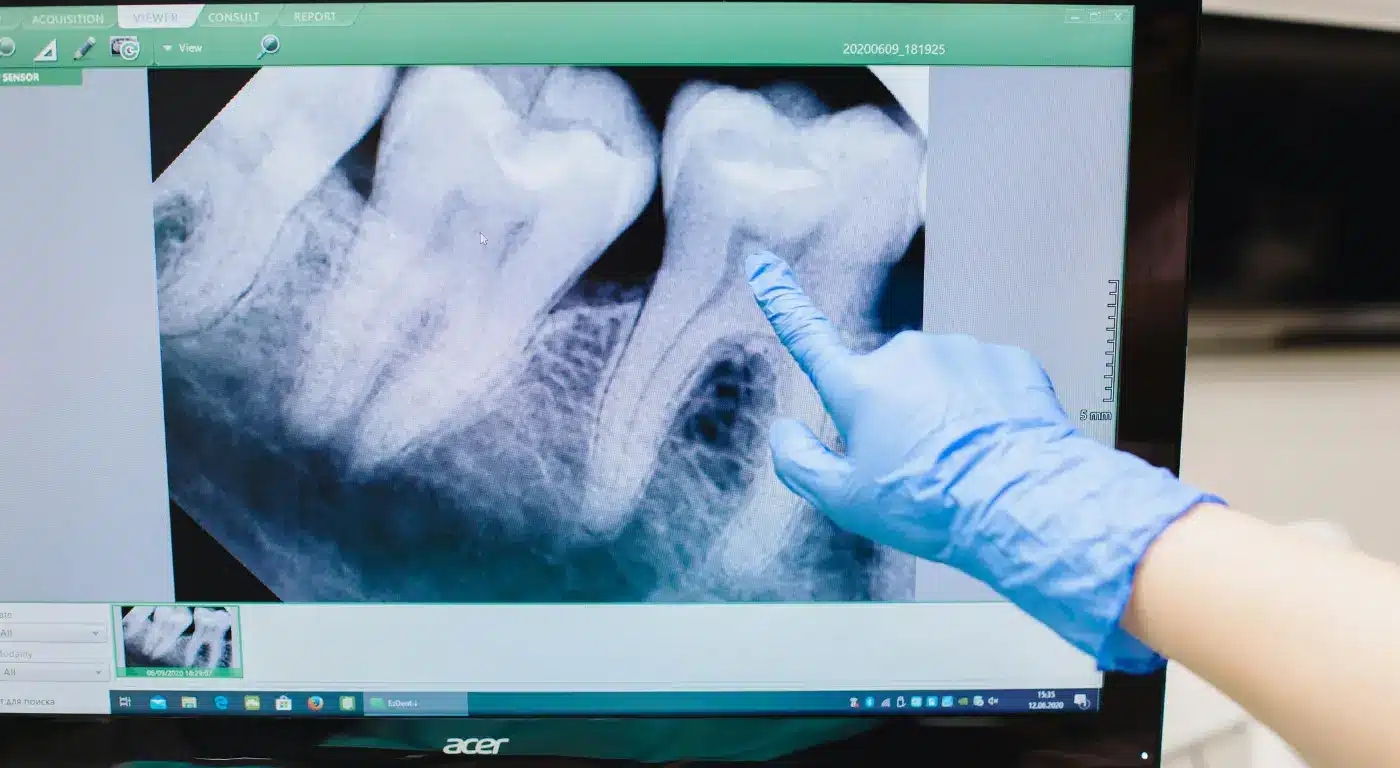

- X-rays: Panoramic X-rays or cone beam CT scans provide a detailed view of the position, angle, and roots of your wisdom teeth, as well as their relationship to nerves and other structures. This imaging is crucial for planning the wisdom tooth removal surgery.